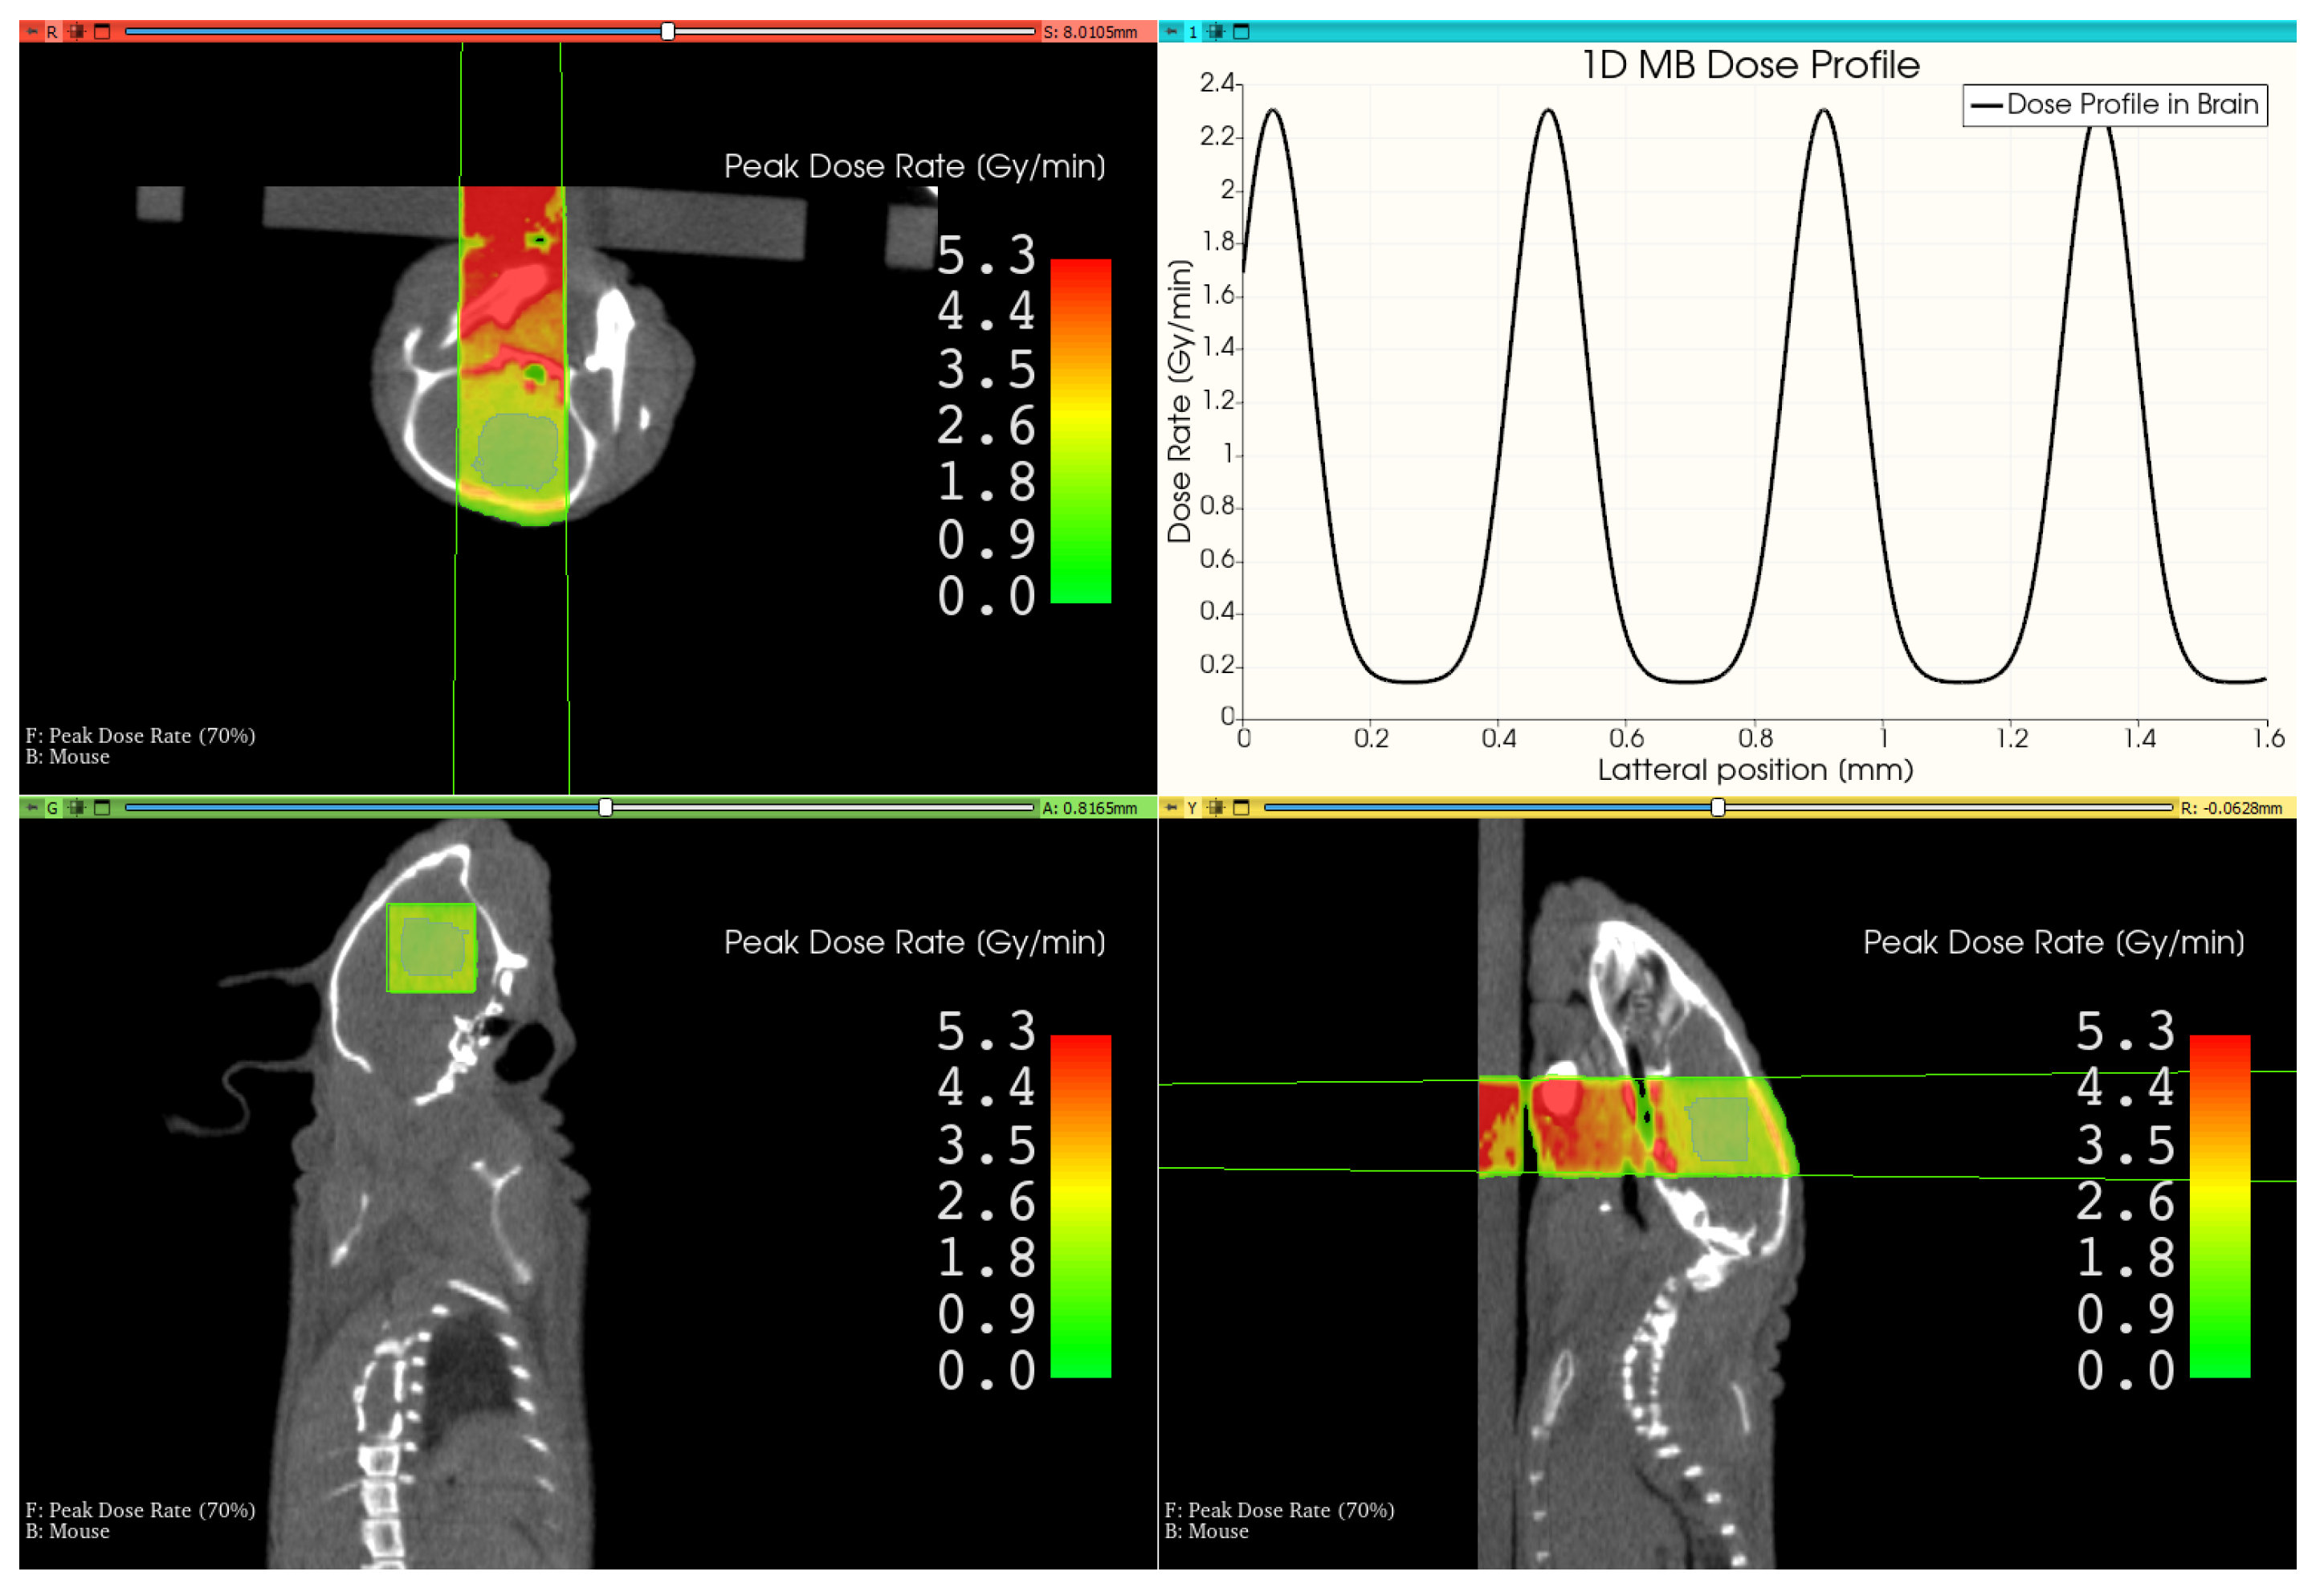

3.3. Therapy Plan for a Mouse Treatment